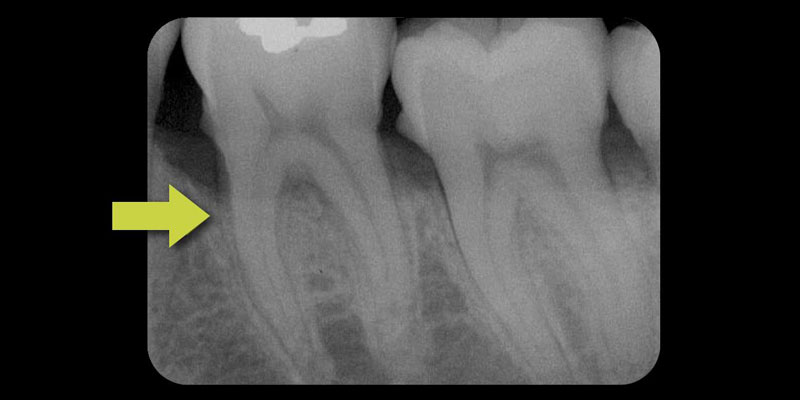

Periodontal defects include the intrabony and furcation-type defects, as well as with gingival recession or loss of attachment. The periodontal literature validates the regenerative potential of biologically active bone replacement grafts (Figs. 1–5).5, 6, 7 Periodontal regeneration with histological evidence of new cementum, periodontal ligament and alveolar bone has been shown in the human model with a recombinant growth factor and a porcine (pig)-derived protein.8, 9, 10

The ability to reconstruct the tissues in an area that was previously infected by periodontitis serves as the ultimate acid test for regenerative achievement. Human recombinant platelet-derived growth factor (PDGF-BB), a protein that regulates cell growth and division, and beta tricalcium phosphate (β-TCP), a drug delivery system for bone, have been shown to accelerate clinical attachment level gains and significantly increase bone growth in severe periodontal defects.11 Recombinant human platelet-derived growth factor (rhPDGF-BB) and enamel matrix derivative (EMD) have demonstrated tissue regeneration when used adjacent to a previously diseased root surface.8, 9, 10